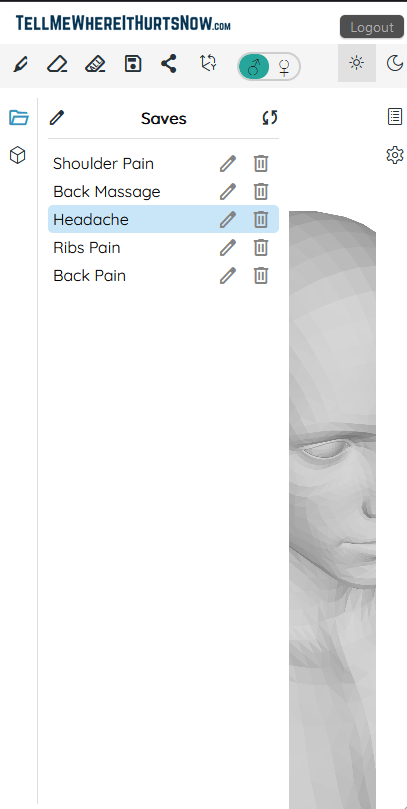

TellMeWhereItHurtsNow: Web app for visual pain communication. Mark areas on 3D body model, show intensity, share with doctors. Track pain over time. Works on all devices. Show doctors exactly where it hurts to improve communication and understanding.